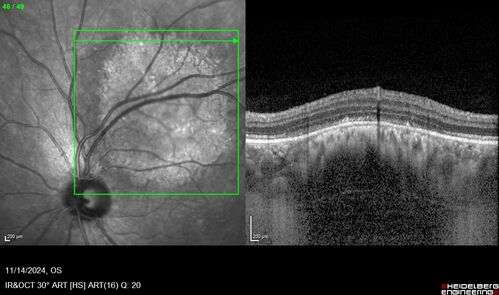

Small choroidal melanoma

28 year old man Serial images suggested that the lesion is growing

OD: sc20/16

OS: sc20/40+2

IOP: TP: OD:19 OS:16